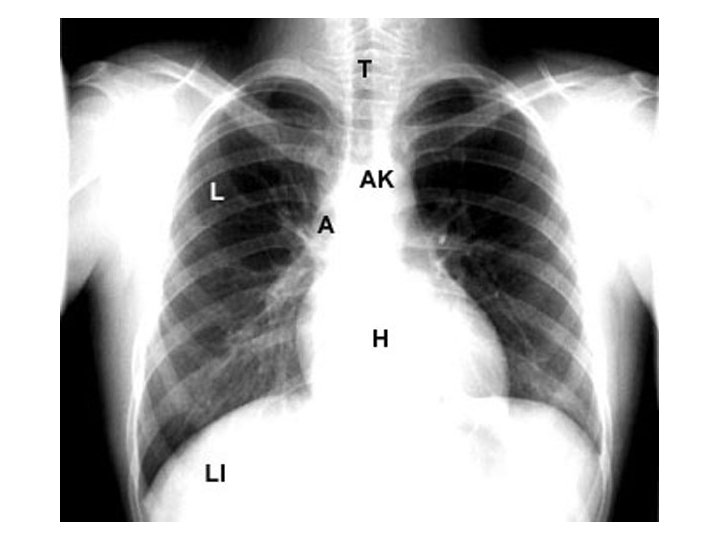

Chest X-ray Path correlation • • • Normal structures Densities Genesis of abnormal densities

Chest X-ray Path correlation • • • Normal structures Densities Genesis of abnormal densities Localization Pathological correlation Steps in evaluation of CXR

Left RV RA LV LA